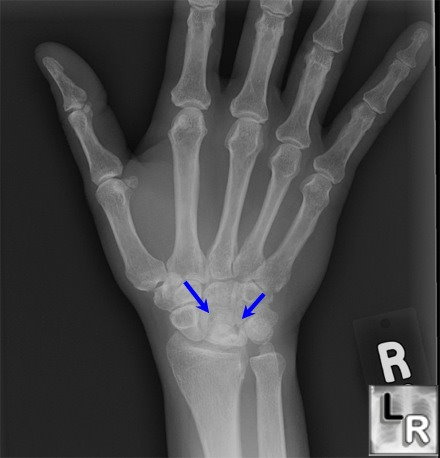

What stage is this disease at?

Stage 4

What does the Crescent sign indicate in avascular necrosis of the femoral head?

A crescent-shaped lucent subchondral fissure indicating a fracture line; seen best in abducted position.